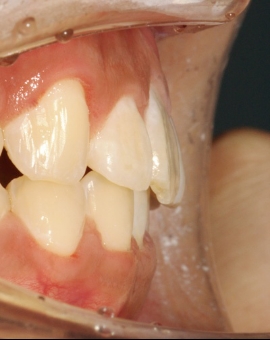

治疗后

治疗前后对比